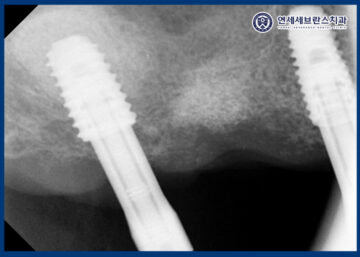

25.07.16 / 25.10.24

이렇게 전체적으로 치유기간을 기다린 뒤

위쪽 부위는 2차 수술을 진행하여

잇몸 안에 매식되어 있던

임플란트 나사를 잇몸 밖으로

노출시켰습니다.

이를 통해 이후 보철 치료를 위한

준비 단계를 진행할 수 있는

상태로 전환하였습니다.